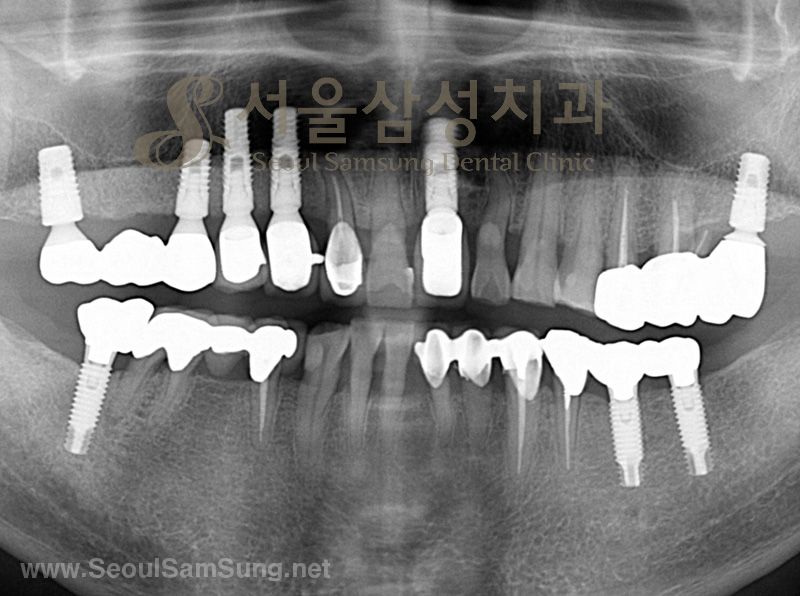

Ʋ´Ï »ç¿ë ÇϽôٰ¡

º»¿ø¿¡¼­ ÀÓÇöõÆ® ½Ã¼úÀ» ¹ÞÀº½Å

ȯÀÚºÐÀÇ ÀÓ»ó»çÁøÀÔ´Ï´Ù.

Ʋ´Ï »ç¿ëÁß ³»¿øÇϽЏð½À

ÀÓÇöõÆ® ¿Ï¼ºµÈ ¸ð½À